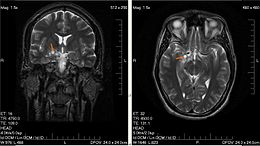

UCLA的研究人员发现将UCLA开发的一种疫苗与其他实验性疗法及FDA批准的疗法联合在一起可以减小晚期脑胶质瘤的大小。这种特异性靶向脑胶质瘤的免疫疗法叫做自体肿瘤裂解液激活的...